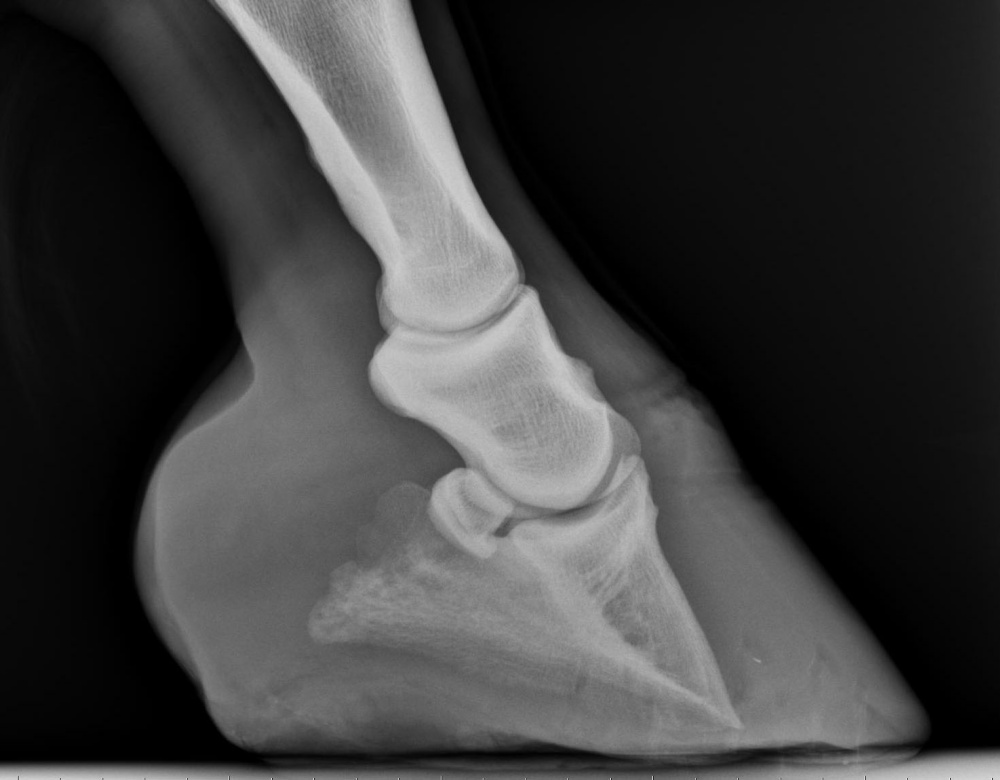

X-ray showing equine foot with capsular rotation

X-ray showing capsular rotation.

Laminitis is a major vascular crisis that results in inflammation and weakening of the laminal structures and bonds within the horses hoof. The damage to the hoof tissue could be severe and may cause rotation and sinking of the pedal bone.

• The pedal bone is no longer supported by laminal structure and begins to rotate and descend towards the sole.